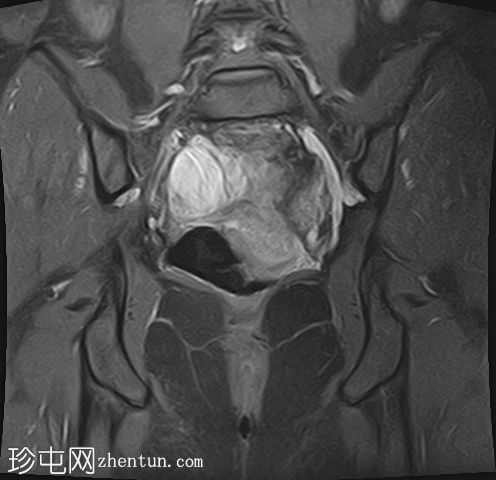

冠状位T1加权像

增强脂肪抑制像

在右侧附件区可见一较大病灶,最大轴位和头尾径约为3 x 3.8 x 3.7 cm。该病灶在T1加权像上呈高信号,脂肪抑制像上无信号抑制,在T2加权像上呈低信号(阴影效应)。病灶壁可见T2暗点征结节,增强扫描后未见明显强化。

右侧附件区可见两个较小的类似病灶,最大径约1.2 cm。

所描述的右侧附件病灶具有典型的子宫内膜异位囊肿MRI特征,包括T1高信号(无脂肪抑制)和T2低信号(阴影)。T2暗点征的存在进一步支持慢性出血性内容物。

相关的较小病灶可能代表其他子宫内膜异位种植灶。